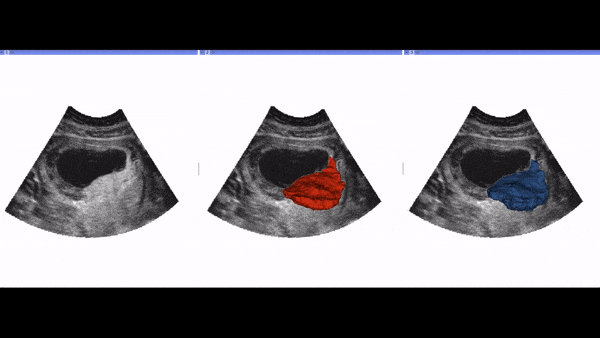

Automated segmentation to estimate placental volume

Fully automated, real-time 3D ultrasound segmentation to estimate first trimester placental volume using deep learning

We present a new technique to fully automate the segmentation of an organ from 3D ultrasound (3D-US) volumes, using the placenta as the target organ. Image analysis tools to estimate organ volume do exist but are too time consuming and operator dependant. Fully automating the segmentation process would potentially allow the use of placental volume to screen for increased risk of pregnancy complications. The placenta was segmented from 2,393 first trimester 3D-US volumes using a semiautomated technique. This was quality controlled by three operators to produce the “ground-truth” data set. A fully convolutional neural network (OxNNet) was trained using this ground-truth data set to automatically segment the placenta. OxNNet delivered state-of-the-art automatic segmentation. The effect of training set size on the performance of OxNNet demonstrated the need for large data sets. The clinical utility of placental volume was tested by looking at predictions of small-for-gestational-age babies at term. The receiver-operating characteristics curves demonstrated almost identical results between OxNNet and the ground-truth). Our results demonstrated good similarity to the ground-truth and almost identical clinical results for the prediction of SGA.